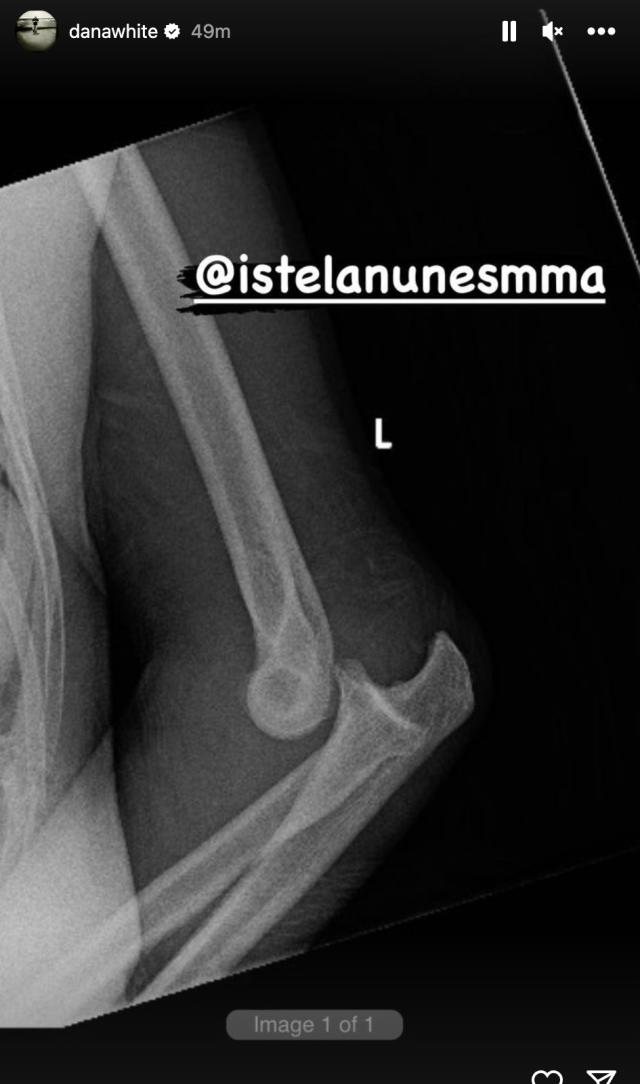

UFC president Dana White later shared an image of Nunes’ X-ray.

The image appears to show a complete dislocation of the elbow’s ball from its socket. An official diagnosis wasn’t provided.